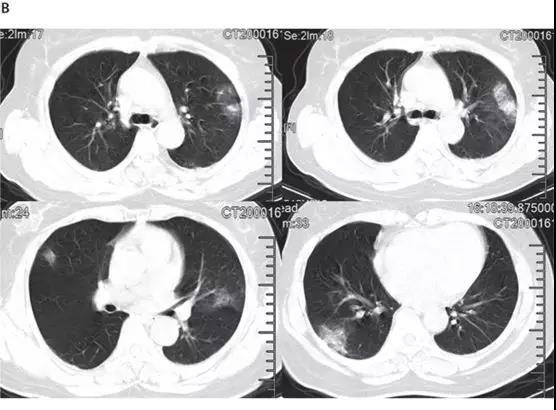

非ICU患者的代表性胸部CT檢查表現為雙側毛玻璃樣混濁和亞段實變(見下圖)。